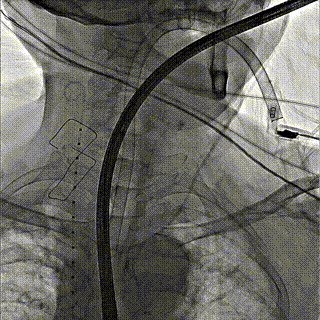

团队前期经过多次讨论,制定了周密的手术策略和预案。由于患者已是近九旬的超高龄老人,传统外科开胸手术风险极高,纯介入经血管三尖瓣替换能够明显减少创伤。术中陈茂及冯沅教授结合体表定位在造影指示下精准穿刺右侧颈静脉并预置两把血管缝合器。成功建立经皮血管入路后在食道超声和DSA的引导下顺利完成人工瓣膜植入,术后超声和造影显示人工三尖瓣同轴性良好,瓣架固定牢靠,无反流和瓣周漏,平均跨瓣压差降为1mmHg。术毕收紧预置的血管缝合器缝线完成止血,缝合效果满意,在手术室即刻拔除气管插管。

术中操作

术前DSA造影

术后DSA造影

颈静脉穿刺造影